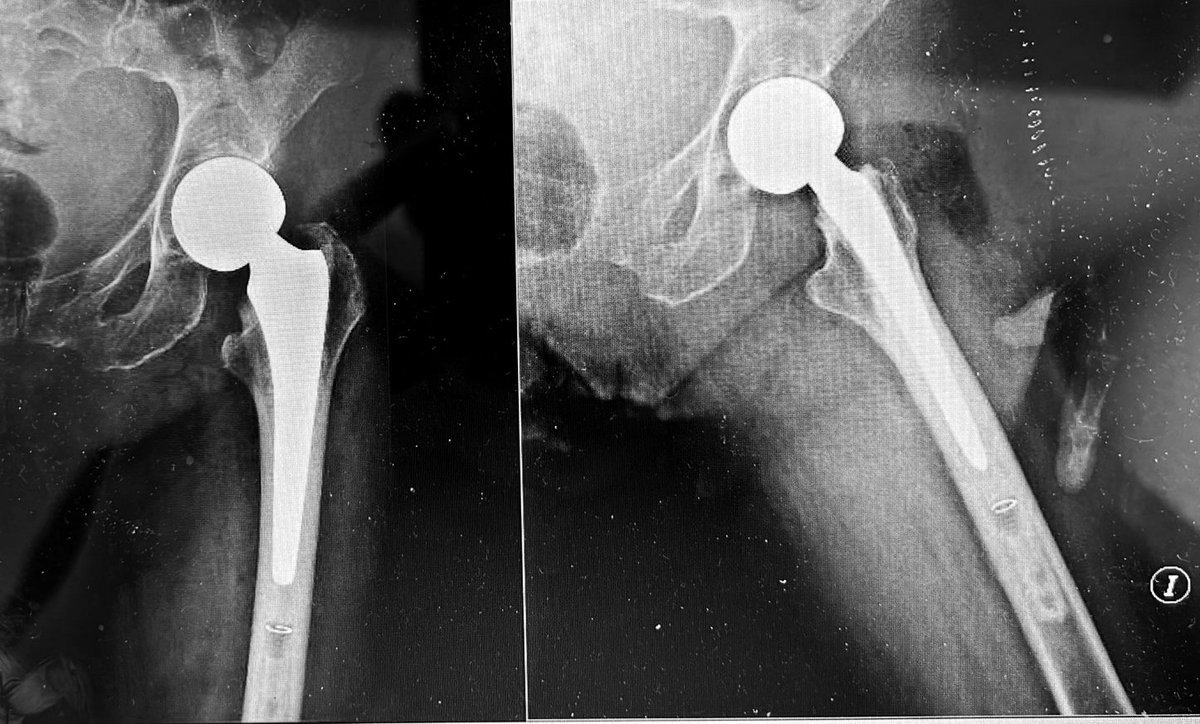

Day 2, case 2: infected femur non-union with shortening. Plan: debridement and irrigation with hardware removal. Circular external fixation for deformity correction and treatment of non-union. Will accept shortening for now.

@MirnaOchoa13 @RiceOlivia